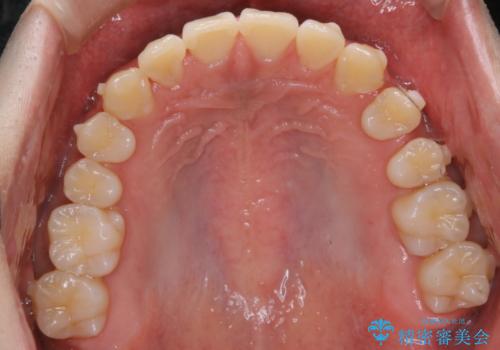

- 前歯のがたつきが気になるとご相談にいらした方です。左の奥歯の噛み合わせのズレも認められたため、インビザライン治療にて改善しました。

主訴である前歯のガタつきだけでなく、奥歯の噛み合わせからしっかり治療したため、治療期間が長めとなりました。患者様ご本人としては治療の途中で一時的にモチベーションが下がったこともあったようですが、最後まで頑張って続けて頂けたことで噛み合わせ及び見た目の改善を行うことが出来ました。